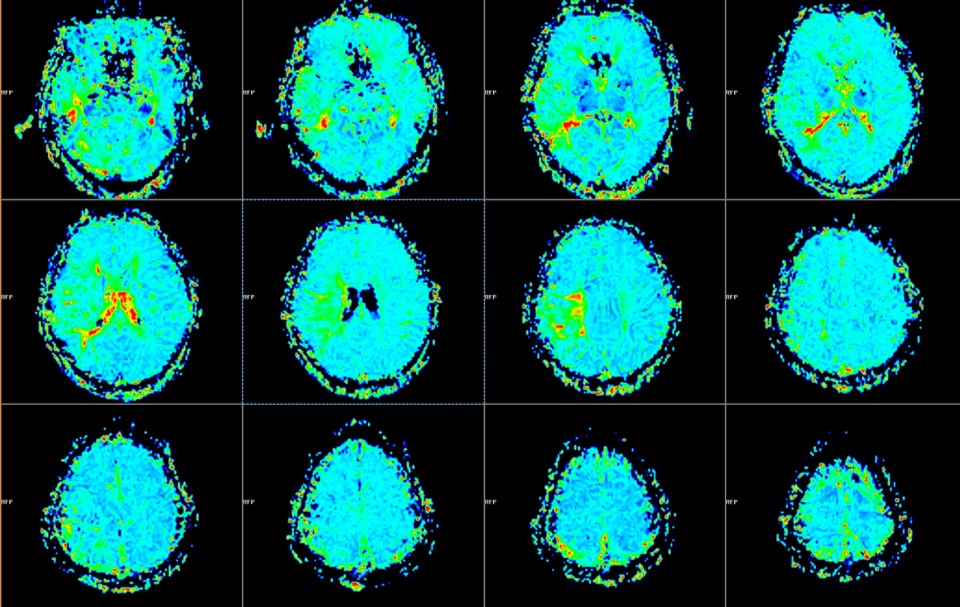

PWI显示:右侧颞叶、半卵圆区、顶下小叶MTT延长。

PWI显示:右侧颞叶、额叶下部、半卵圆区、顶叶PTT延长。

术后1周MRI PWI显示:右侧颞叶、半卵圆区、顶下小叶MTT较术前改善。

PWI显示:右侧颞叶、额叶下部、半卵圆区、顶叶PTT延长范围较术前缩小。